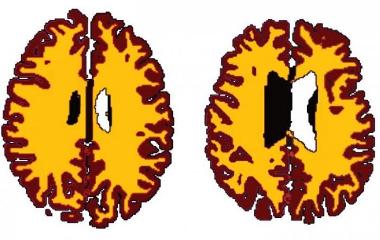

Исследование, опубликованное в журнале Neurobiology of Aging, показало, что у взрослых среднего возраста с избыточным весом объем белого вещества в мозге меньше по сравнению с теми, у кого вес в норме.

Исследователи оценили церебральный объем белого и серого вещества участников с использованием магнитно-резонансной томографии (МРТ). По сравнению с худыми участниками, у испытуемых с избыточным весом или ожирением выявлено значительное уменьшение объема белого вещества.

Затем исследователи рассмотрели, как объем белого вещества связан с возрастом и весом испытуемых. Они обнаружили, что избыточный вес и ожирение, как представляется, оказывают наиболее пагубное воздействие на мозг людей среднего возраста.

Объем белого вещества у взрослых среднего возраста с избыточным весом или ожирением сопоставим с объемом у худых, которые были на 10 лет старше. Например, объем белого вещества у 50-летнего взрослого с избыточным весом был на одном уровне с 60-летним худым.